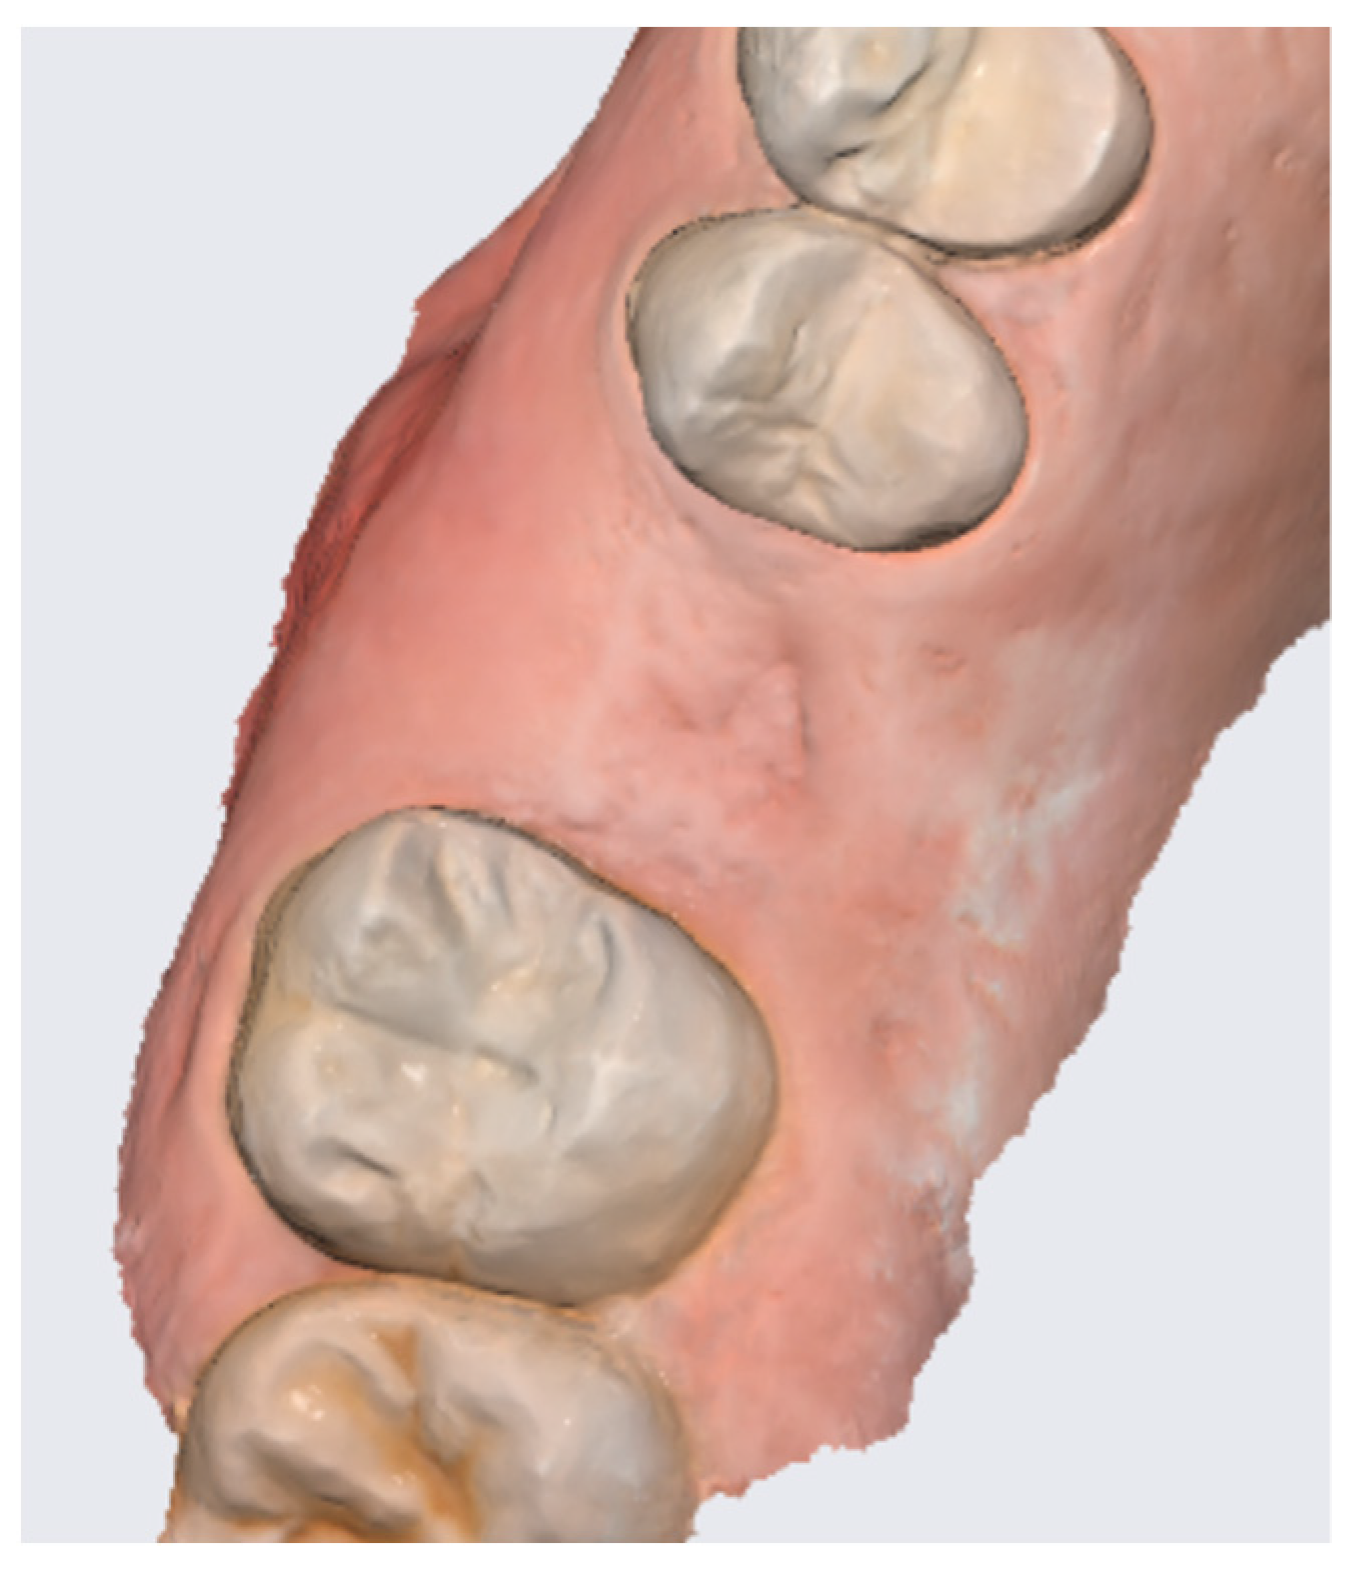

2.6. Case Presentation. Nano-HA Applied to Socket Preservation Procedures

3. Results